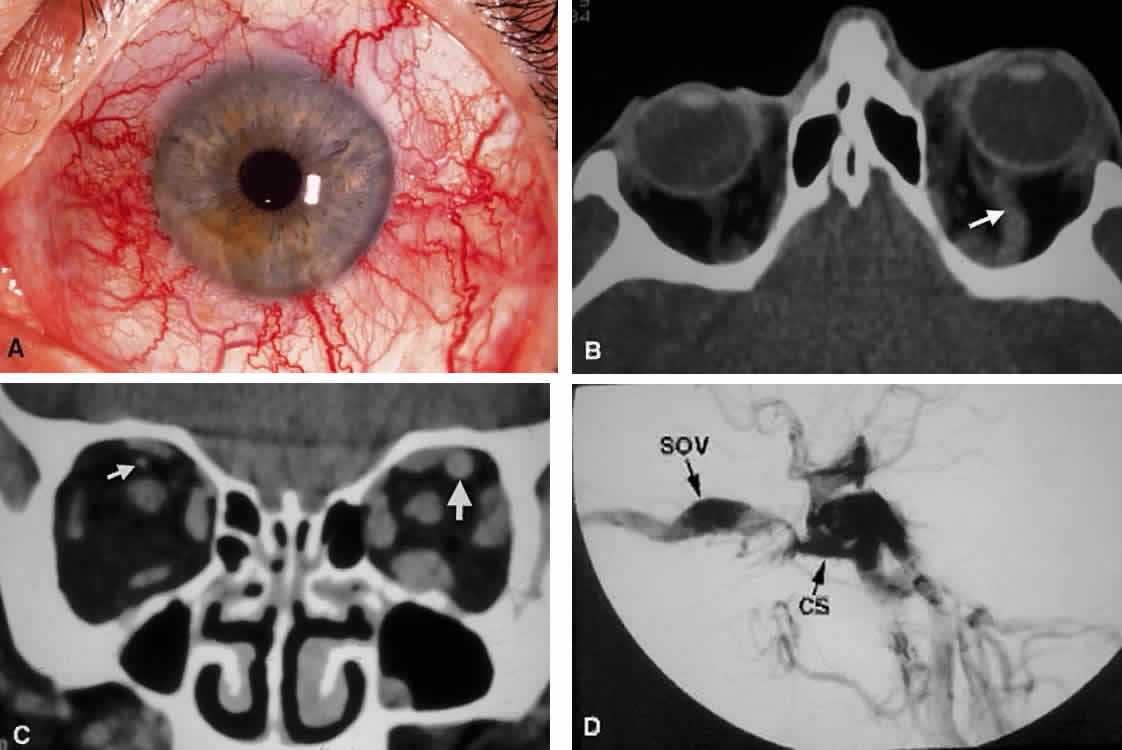

Before giving off the ophthalmic artery, the ICA has several minor branches that supply the meninges, including the dura of the lateral wall of the CS. An abnormal communication between the arterial and venous supply of the CS results in either a carotid-cavernous fistula or a dural-sinus fistula (Fig. 18A). Because of the larger caliber of the ICA, a carotid-cavernous fistula is usually symptomatic secondary to a high flow state, possibly manifesting as orbital/ocular ischemia and increased intraocular pressure. This type of fistula is most commonly encountered in younger patients after blunt trauma and may require invasive neuroradiologic treatment (Fig. 18B). Conversely, a dural-sinus fistula is typically a low-flow state because the abnormal communication forms between the small-caliber dural arterial feeders of the lateral CS wall and the venous plexus of the CS. Such fistulas are usually seen in older individuals as a spontaneous event. Depending on the severity of symptoms, most dural sinus fistulas are simply followed by observation because of the high rate of spontaneous closure.

Fig. 18. Carotid-cavernous fistula. A. Clinical photograph demonstrating tortuosity of the arteriolized episcleral veins, extending up to the limbus (the vascular congestion of conjunctivitis usually ends 1 mm short of the limbus). B. Axial CT shows the difference in caliber between the uninvolved superior ophthalmic vein and the involved vein (arrows). C. Coronal image likewise shows the difference in venous size (arrows). Also note the enlargement of the extraocular muscle on the involved side, indicative of orbital congestion. The superior ophthalmic vein is always found beneath the superior rectus muscle, to which it is tethered by a hammock-like fascial slip. On the involved side, orbital congestion and enlargement of the vein cause distortion of this anatomic relation. D. Parasagittal arteriography image of a different patient shows abnormal arterial filling of the CS, extending anteriorly into the orbit through an engorged superior ophthalmic vein (SOV).